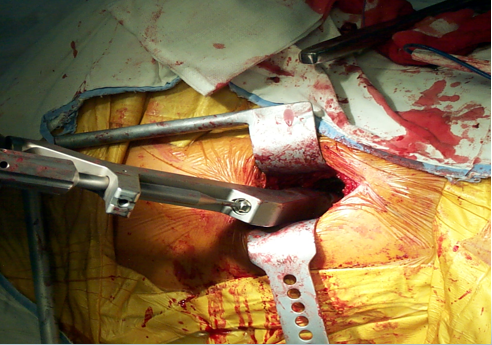

Hueter入路:髂前上棘后2cm到腓骨头方向切口10-15cm沿阔筋膜张肌和股直肌间隙直接到达前方关节囊

Hardinge入路股骨大粗隆中点上下8-10cm纵行切开阔筋膜张肌和髂胫束

沿臀中肌前1/3肌纤维方向切至股外侧肌前1/3

肌瓣下方即为前方关节囊

后外侧入路屈髋45º,大粗隆中点上下10cm纵行切开阔筋膜张肌和髂胫束大粗隆后缘切断外旋肌群

髂脊最高点后2横指到大粗隆连线切口7-8cm70%在粗隆近端,30%在粗隆远端

切开臀大肌和阔筋膜髋关节内收内旋切断梨状肌、股方肌暴露后方关节囊

大粗隆下2cm为中点后上到前下30º切口长7-9cm

沿阔筋膜纤维方向切开扩筋膜大粗隆顶点臀中肌前1/3处沿纤维方向分离臀中肌

横形切开臀小肌2cm

沿大粗隆前缘切开臀中肌腱和臀小肌

切除关节囊髋关节内收、屈曲、外旋位脱位